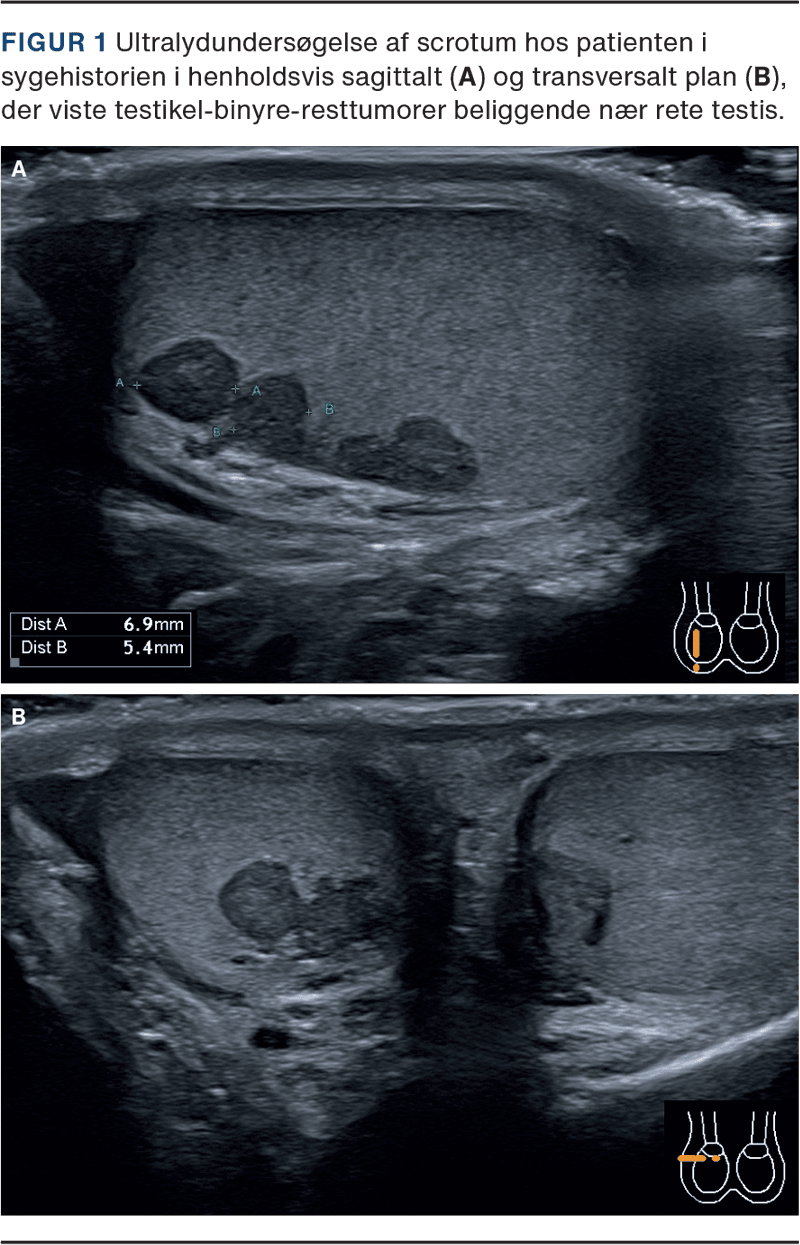

En mand i slutningen af 20’erne blev som tilflytter til kontrolforløb for kendt, klassisk AGS henvist til en lokal, endokrinologisk klinik. Han havde i længere perioder haft nedsat adhærens til behandlingen med hydrocortison og fludrocortisonacetat og havde flere indlæggelseskrævende episoder af akut binyrebarkinsufficiens bag sig. Undervejs fandtes biokemisk, hypogonadotrop hypogonadisme og let størrelsesreducerede testikler bilateralt. Ved ultralydundersøgelse (UL) af scrotum fandt man flere tumorer i testiklerne foreneligt med diagnosen testikel-binyre-resttumorer (testicular adrenal rest tumours, TART) (Figur 1). Efterfølgende forbedret adhærens til hydrocortisonbehandlingen normaliserede niveauerne af ACTH og androgene hormoner inkl. testosteron. Ved gentagne målinger blev der fundet normalt niveau af inhibin B, indikerende bevaret sertolicellefunktion og spermatogenese.

TART er godartede læsioner i testiklerne ved vedvarende forhøjet ACTH-niveau ved AGS, ofte forårsaget af underbehandling med hydrocortison. Fraværet af symptomer ved under- eller helt manglende behandling skyldes en vis, bevaret enzymaktivitet, og hos disse patienter opleves symptomatisk binyrebarkinsufficiens derfor først under interkurrent sygdom. TART antages at stamme fra pluripotente celler med karakteristika for både binyrebark- og Leydigceller, beliggende i testiklerne. TART findes, med betydelig usikkerhed på estimatet, hos ca. 40% af drenge og unge mænd med AGS [2]. Ved UL, der anbefales rutinemæssigt ved klassisk AGS, fremstår TART som typisk ensartede, bilaterale og velafgrænsede hypoekkogene læsioner beliggende nær mediastinum testis [3]. Disse karaktertræk er vigtige differentialdiagnostisk over for maligne læsioner, og for at undgå unødvendige biopsier og kirurgisk intervention [4].